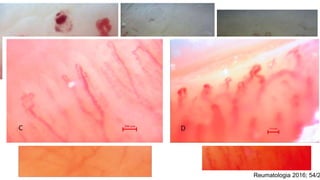

Figure 5: Enlarged capillary loops;

(A) normal capillary loop,

(B) enlarged afferent capillary loop, (C)enlarged efferent capillary

loop,

(D) enlarged apical capillary loop, (E) horseshoe shape giant